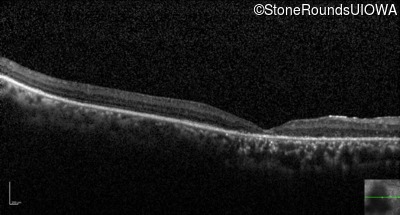

Optical Coherence Tomography - Right - 20/400 sc

Exemplar / OCT Stack

Optical Coherence Tomography - Left - 20/1000 sc